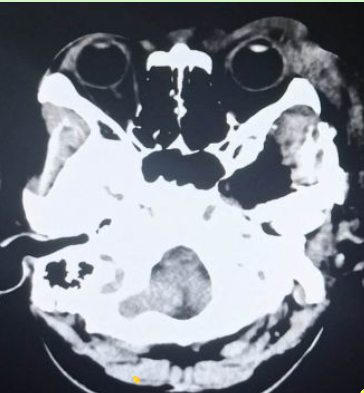

颅脑核磁示:左侧颞下窝占位。

术前CT显示肿瘤和扩大的卵圆孔